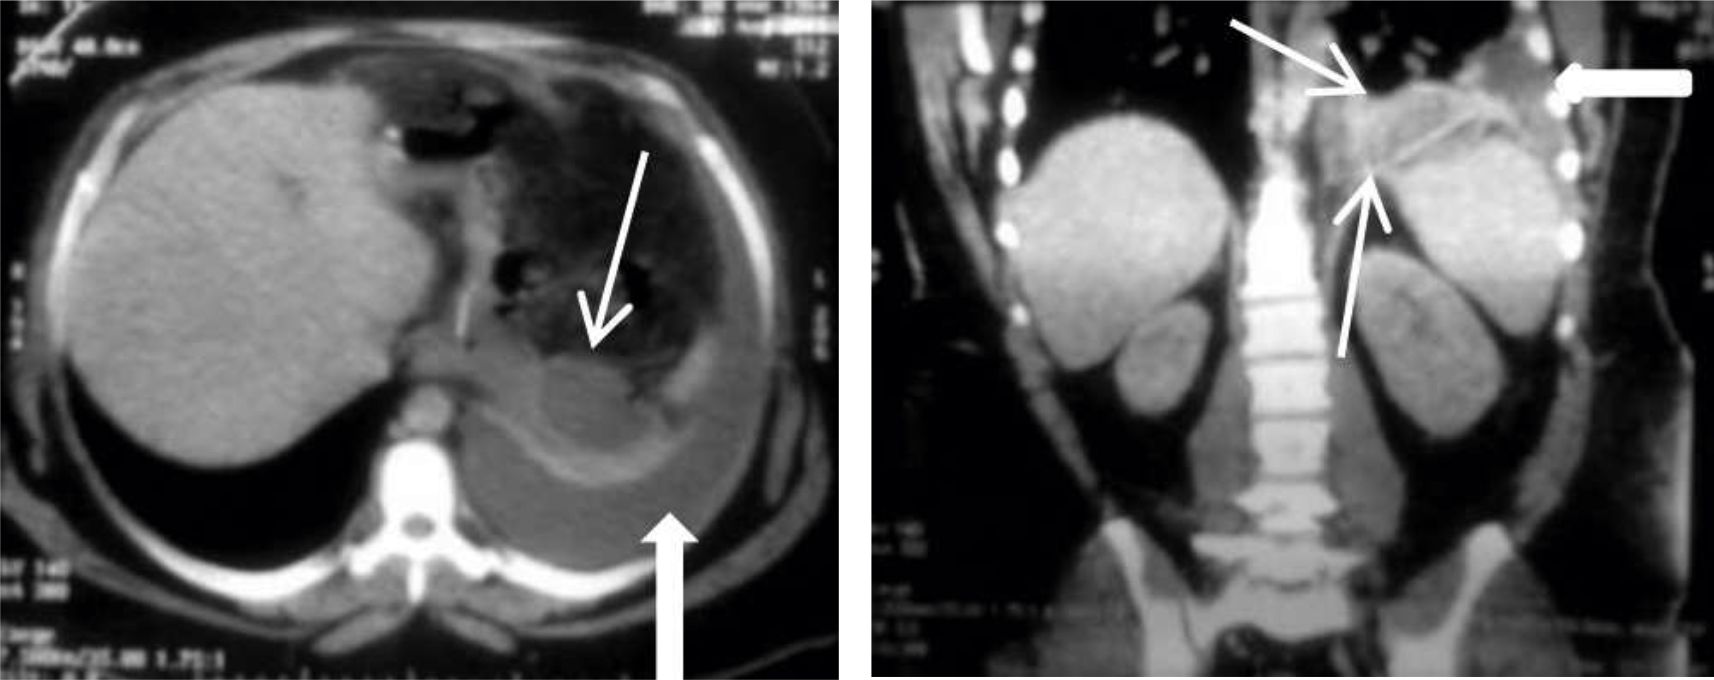

Figura 4

EGD en proyección AP

donde se observa trayecto fistuloso filiforme superior izquierdo (flecha fina) con pequeña colección en su sector distal (flecha curva) y catéter de drenaje laparoscópico (flecha gruesa). (Paciente Nº 14)

Figura 5

EGD de control en proyección AP

donde se observa el trayecto de una fístula enterocutánea (flechas). (Paciente Nº3)

Figura 6

Paciente que al 3er día del postoperatorio refiere dolor abdominal.

Se realiza una TC con contraste i/v que evidencia alteracion de a grasa perigástrica.

EGD del mismo paciente que muestra en la evolución un trayecto fistuloso lateral derecho (flecha fina) con catéter de drenaje (flecha gruesa).(Paciente Nº4)

La principal utilidad del estudio de EGD post-operatorio es el seguimiento evolutivo de las fugas drenadas hasta su cierre. Figuras 4,5 y 6.